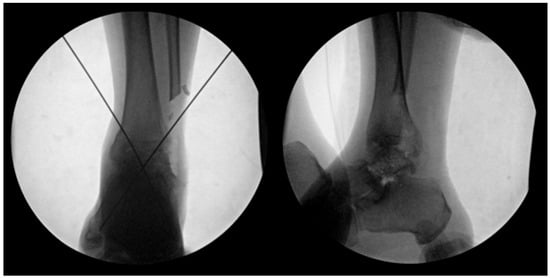

Preoperative surgical planning was initiated through detailed CT and plain radiographic evaluation of the contralateral, unaffected talus to determine the most appropriate size and shape of the allograft. This templating process included measurement of the maximum vertical height from the apex of the talar dome to the posterior facet (on the lateral view), the anteroposterior length of the talar head (on the superior view), and the maximal mediolateral width (Figure 1). These dimensions were used to estimate the optimal talar geometry. Additionally, patient-specific factors such as body height, body mass, and limb laterality were considered to enhance size matching accuracy. These preoperative measurements were then compared against a catalog of available cadaveric talus allografts from the national tissue bank to identify a suitable donor match. Once selected, the appropriate-sized fresh–frozen talus allograft was reserved and procured for intraoperative use. As of 2023, the cost of an allogeneic talus through the Korea Public Tissue Bank is approximately EUR 400, whereas, a femoral head allograft suitable for talar reconstruction costs approximately EUR 480.

Figure 1. Preoperative measurements were performed using standard radiographs of the contralateral, unaffected talus to guide selection of an appropriately sized allograft. Key anatomical dimensions include: (L) mediolateral width measured across the talar body in the superior view; (W) anteroposterior length from the talar head to the posterior margin in the superior view; (H) maximum vertical height from the apex of the talar dome to the posterior facet in the lateral view. These measurements were used to select the most anatomically compatible allograft from the national tissue bank for each patient.